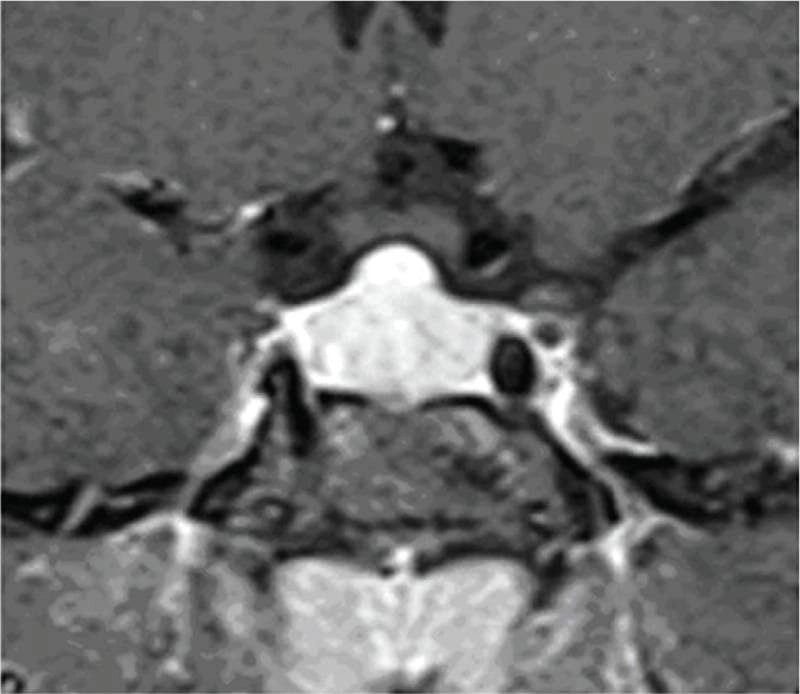

তবে পিটুইটারি হাইপারপ্লাসিয়া দেখা যায় প্রাইমারি গনাডাল, অ্যাডরিনাল বা হাইপোথাইরয়েডিজমের মত এন্ড অর্গান ইনসাফিসিয়েন্সিতে। বিশেষ করে, অব্যবহৃত প্রাইমারি হাইপোথাইরয়েডিজমে পিটুইটারি হাইপারপ্লাসিয়া পূর্বের ধারণার তুলনায় অনেক বেশি দেখা যায়। ২০১৯ সাল পর্যন্ত এরকম ১০৫টি কেস রিপোর্ট করা হয়েছে। এই ধরনের হাইপারপ্লাসিয়া গম্বুজ-আকৃতির (dome-shaped) হয়ে অপটিক কায়াজমাকে চেপে ধরতে পারে, যার ফলে অপারেশনের প্রয়োজন পড়তে পারে—যেমনটা আমাদের তৃতীয় কেসে ঘটেছিল।

কেস ৩: এই কেসে, ২৪ বছর বয়সী এক তরুণীকে পিটুইটারি টিউমার সন্দেহে অপারেশন করা হয় এবং পরদিন হরমোনাল চিকিৎসার জন্য রেফার করা হয়, যিনি অপারেশনের পর ডায়াবেটিস ইনসিপিডাসে আক্রান্ত হন। পরবর্তী বিশ্লেষণে তার প্রি-অপারেটিভ TSH ছিল অনেক বেশি এবং MRI তে “ডোম-আকৃতির” পিটুইটারি বড় হওয়া দেখা যায়। অপারেশন এড়ানো সম্ভব হলে, এ রোগীও ওষুধেই সুস্থ হতে পারতেন। এরকম টিউমার সন্দেহে অপারেশনের নিদর্শন বিশ্বযুরে একাধিক রয়েছে এবং বলাবাহুল্য এ ধরনের অপ্রয়োজনীয় অপারেশনের পরে রুগীরা আজীবন বন্ধ্যাত্ব এবং একাধিক হরমোন ঘাটতির কারণে জীবনভর ভুগতে হয়। ভাগ্যক্রমে, এই রোগীটির ক্ষেত্রে অপারেশনের পর তিনি কোনো স্থায়ী নিউরো-হরমোনাল ঘাটতিতে পরেননি।

চিকিৎসক তথা আবিষ্কারক সত্যম তিনটি কেসের বিষয় নিয়ে যখন তুলনা করতে নিলেন এবং পুরনো সৃষ্টি ঘাটতে শুরু করলেন তখন তিনি দেখতে পান সবগুলি ক্ষেত্রেই একই রকম সাদৃশ্য অর্থাৎ পিটুইটারি গ্রন্থি মাঝের অংশ এই গ্রন্থি দেখতে খানিকটা প্রজাপতির মতোই এবং তার মাঝের অংশের (প্রজাপতির দেহের উপরের অংশ মাথার মতই দেখতে) উপরের ভাগ সব ক্ষেত্রেই ডোমের মত বা গম্বুজ আকৃতির। তিনি এই ডোম বা গম্বুজ আকৃতি হওয়ার কারণ বিশ্লেষণ করতে গিয়ে দেখেন পিটুইটারির সামনের অংশ যেখানে থাইরোট্রপগুলো থাকে, যেখান থেকে এই টিউমারটি হয়। আর যখনই এটি বাড়বে তখন টমের মতনই তৈরি হবে। অর্থাৎ গম্বুজ আকৃতির। আর সেখান থেকেই ডোম-সাইনের উৎস অর্থাৎ আবিষ্কার।

MRI-তে এই হাইপারপ্লাসিয়া সাধারণত গম্বুজ-আকৃতির ও সমমিত হয় এবং হোমোজেনাস সিগনাল ইন্টেনসিটি দেখায়, যেখানে সাধারণ নন-ফাংশনাল পিটুইটারি অ্যাডেনোমা নানা আকার ও অসমতা নিয়ে দেখা যায়।

তাঁর দাবি, MRI-তে ‘DOME Sign’ থাকা এবং TSH বাড়তি থাকলে, সেটি হাইপোথাইরয়েডিজম-জনিত হাইপারপ্লাসিয়ার সম্ভাবনার কথা নির্দেশ করে এবং এই রোগীদের শুধুমাত্র লেভোথাইরক্সিন দিয়ে চিকিৎসা করলে পূর্ণ আরোগ্য সম্ভব।